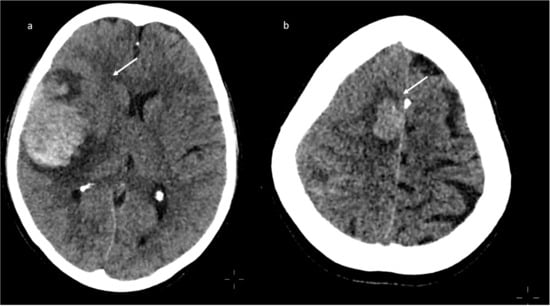

A brain CT performed one day later showed a diffuse ischemic hypodensity involving the right occipito-temporal and the superior cerebellar regions, the right thalamic and internal capsula regions, pons, and mesencephalon (Figure 9), conditioning edema-based mass effect and contralateral shift of the midline structures.

Figure 9.

Brain CT scan: diffuse ischemic hypodensity involving the right occipito-temporal (a) and the superior cerebellar regions, the right thalamic and internal capsula regions, pons and mesencephalon (b).